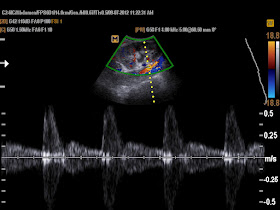

Emergency ultrasound of abdomen: no free fluid, no free air, at the umbilicus there is one mass near the abdominal wall, along from epigatric area to urinary bladder, hyperechoic, no air inside. Pressing over the mass is very painful (2 images of longitudinal and cros-sectional scan at the left umbilicus).